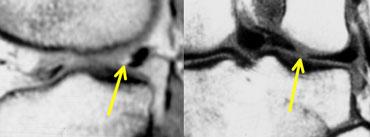

TRÁI: Phim MRI cũ có rách. Bệnh nhân đã được khâu phục hồi. PHẢI: Trên phim MRI mới, có rách mới (mũi tên vàng). Không thể xác định liệu vết rách cũ đã lành hay chưa.

Sụn chêm sau phẫu thuật 2

Bệnh nhân này đã được khâu phục hồi do rách sụn chêm.

Sau đó bệnh nhân bị chấn thương mới.

Trên phim MRI mới, không thể xác định liệu vết rách cũ đã lành hay chưa.

Tuy nhiên, phát hiện thấy rách mới, nên trường hợp này dễ chẩn đoán.

Chụp MRI-khớp: Tại vị trí rách mới, tín hiệu sáng tương đương dịch hoạt dịch (mũi tên vàng). Tại vị trí rách đã lành, tín hiệu không sáng bằng.

Trên ảnh chụp MRI-khớp, vị trí rách mới có cường độ tín hiệu rất cao tương đương dịch hoạt dịch, trong khi vị trí rách cũ đã lành chỉ có cường độ tín hiệu trung bình.

Do đó, so sánh với phim cũ giúp chẩn đoán xác định rách mới, trong khi ảnh chụp khớp cho thấy vết rách cũ đã lành.